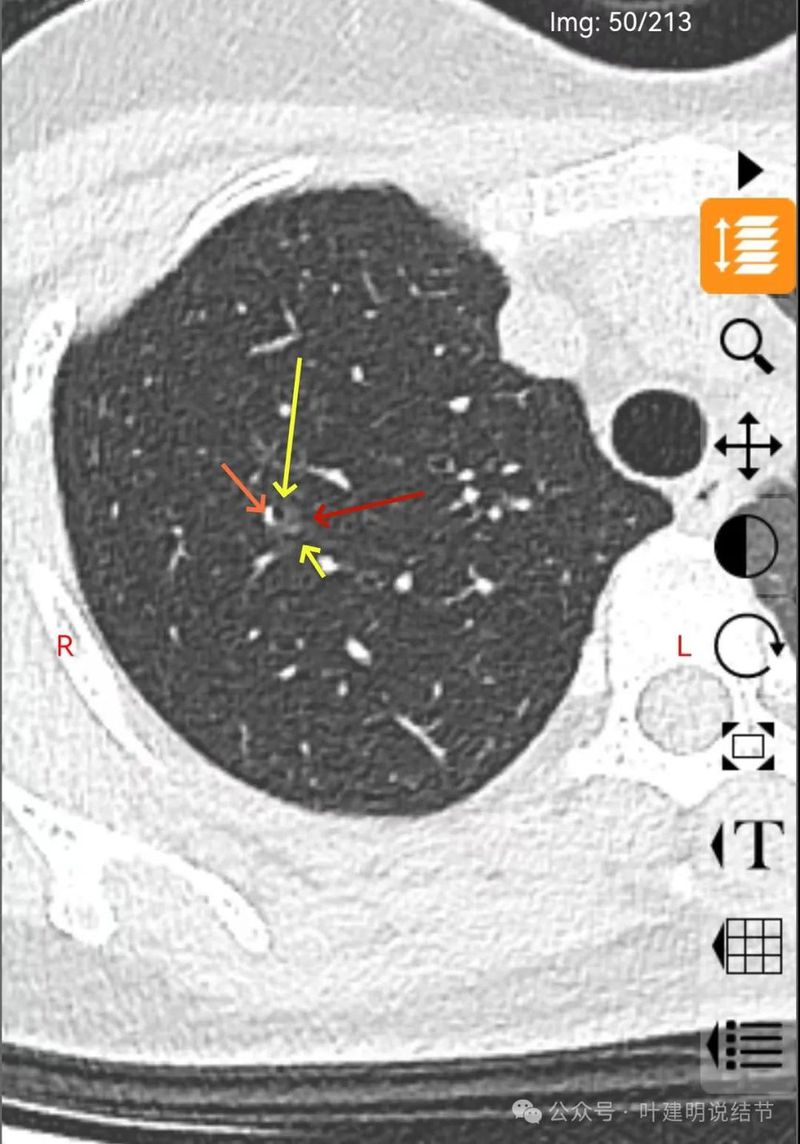

磨玻璃密度伴灶内支气管扩张。

支气管扩张,病灶磨玻璃密度,有血管进入穿行。

边缘处密度较淡。